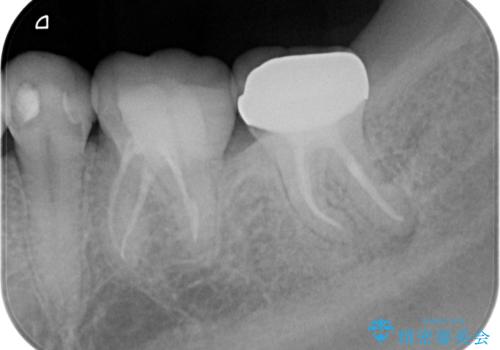

レントゲンや口腔内所見にて以下のような説明ののち、患者様が保存を希望されたため、当院では根管治療~オールセラミッククラウンにて修復処置を行いました。痛みも消えて、経過良好です。

病気の原因は細菌であるため、細菌数を減らすための処置として一般的に②根管治療という選択肢がある。再根管治療の場合は病気が治るのは7割ぐらいであり、それでも治らない場合は意図的再植術を行い9割近くまで成功率を高めることができる。ただし、今回のケースでは根尖が湾曲しているため意図的再植時の破折リスクが高いため適応は難しい。また、根尖の病変が治ったとしても、歯周病、カリエス、脱離や破折リスクがあり治療後抜歯になる可能性もある。治らない可能性や治療したとしても抜歯になる可能性があることを考慮し、③抜歯の選択肢をとる場合もある。